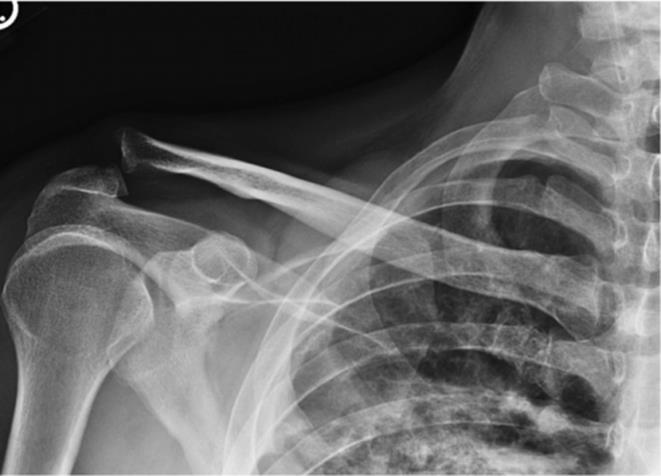

· Plain radiographs are the preferred test for evaluation of suspected humeral shaft fractures (Figure 2.7A, B)

Figure 2.7 A: Humeral shaft fracture. B: Post-reduction film of a humeral shaft fracture stabilized in a coaptation splint. Note the persistent angulation and shortening. (Reproduced with permission of the Department of Emergency Medicine, Feinberg School of Medicine, Northwestern University.)